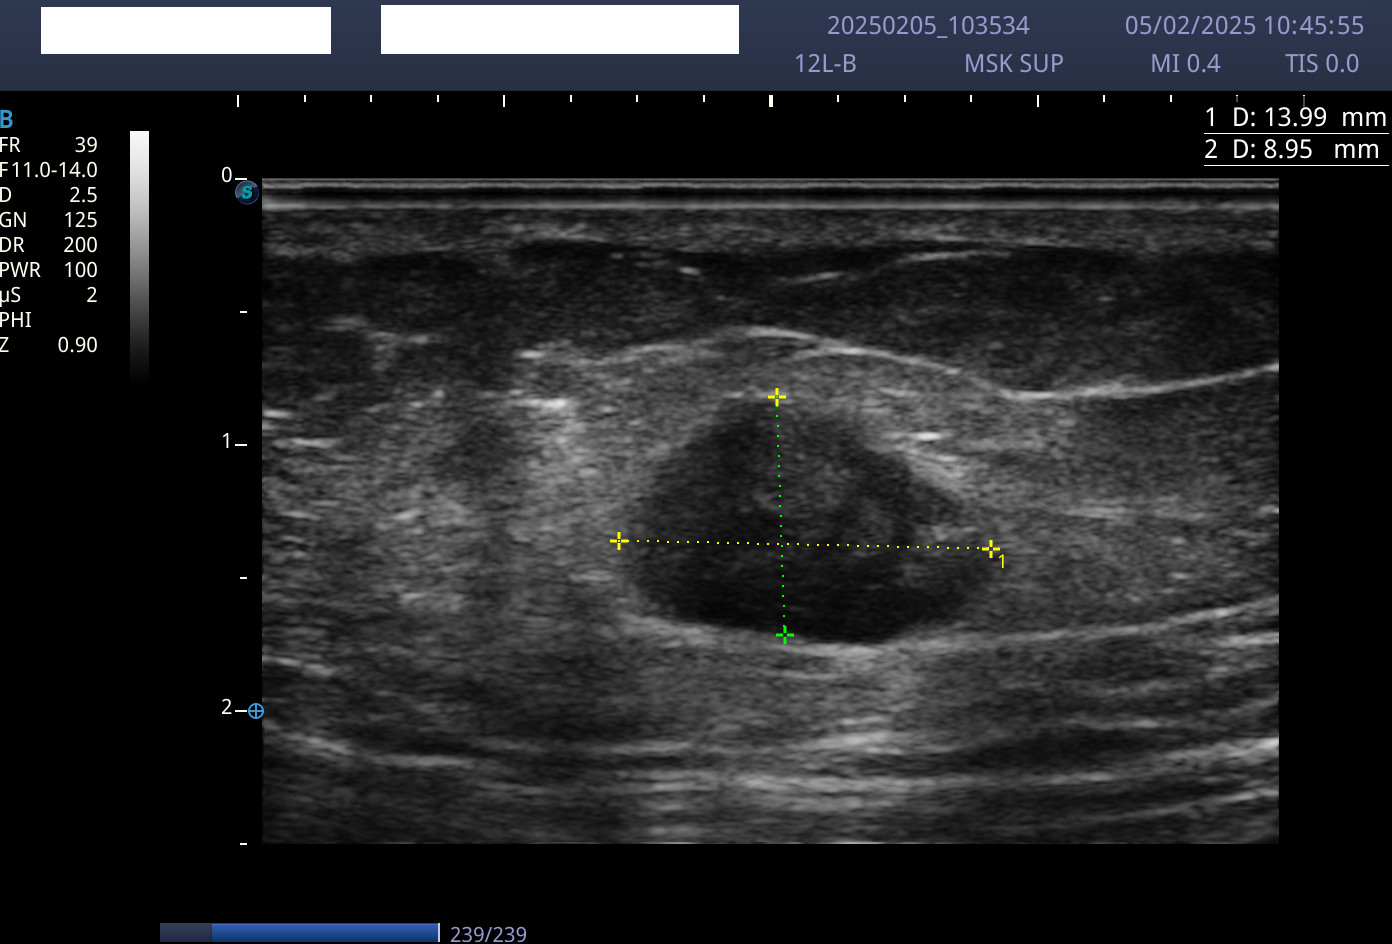

Hallazgos ecográficos

En la ecografía se apreciaron lesiones hipoecogénicas a nivel de plano subcutáneo con bordes mal definidos, sin actividad Doppler.